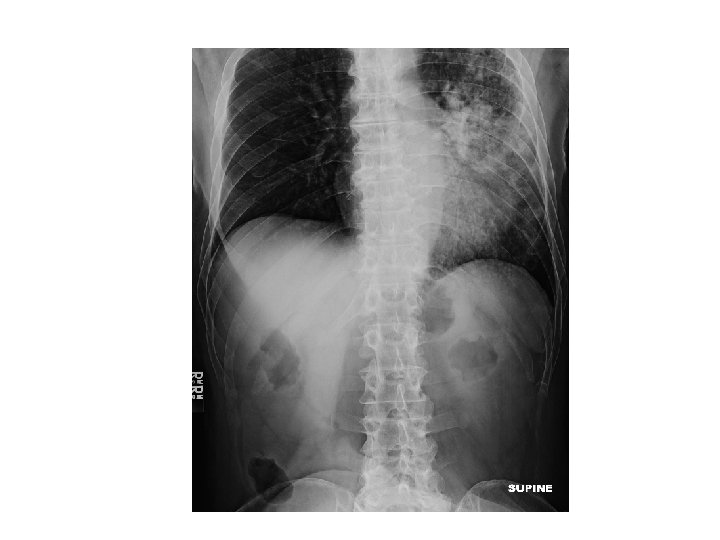

ER work-up • Abdominal XR = No obstruction/ air fluid level Atelectasis with central bronchial obstruction

CT Chest • Multiple cavitary lesions • Largest left lung apex 3. 8 x 4. 7 cm with nodular thickened wall • Smaller cavitary lesions in L lung base • R lung: smaller areas of ground-glass opacities with areas of tree in bud appearance.